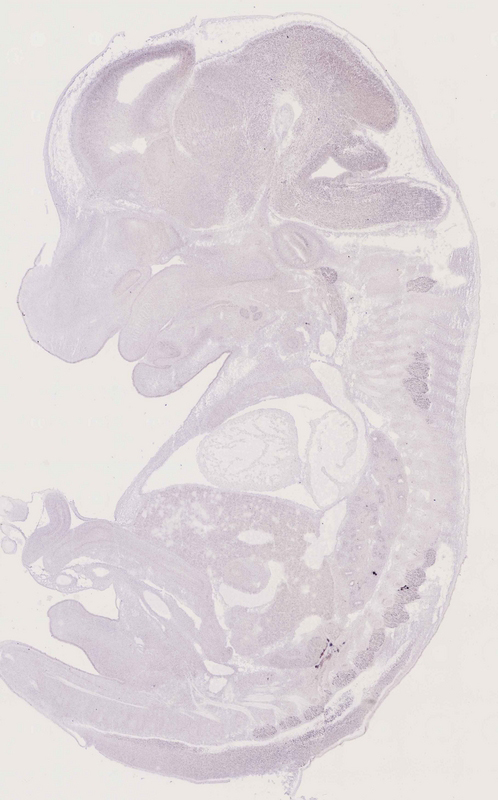

Specimen

euxassay_013785_07:

embryonic day 14.5

euxassay_013785_08: